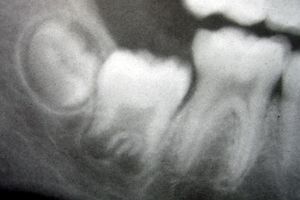

image الإنجليزية

Molarsindevelopment11-24-05.jpg

١٬٨٤٤ × ١٬٢٢٧؛ ٥٣٢ كيلوبايت